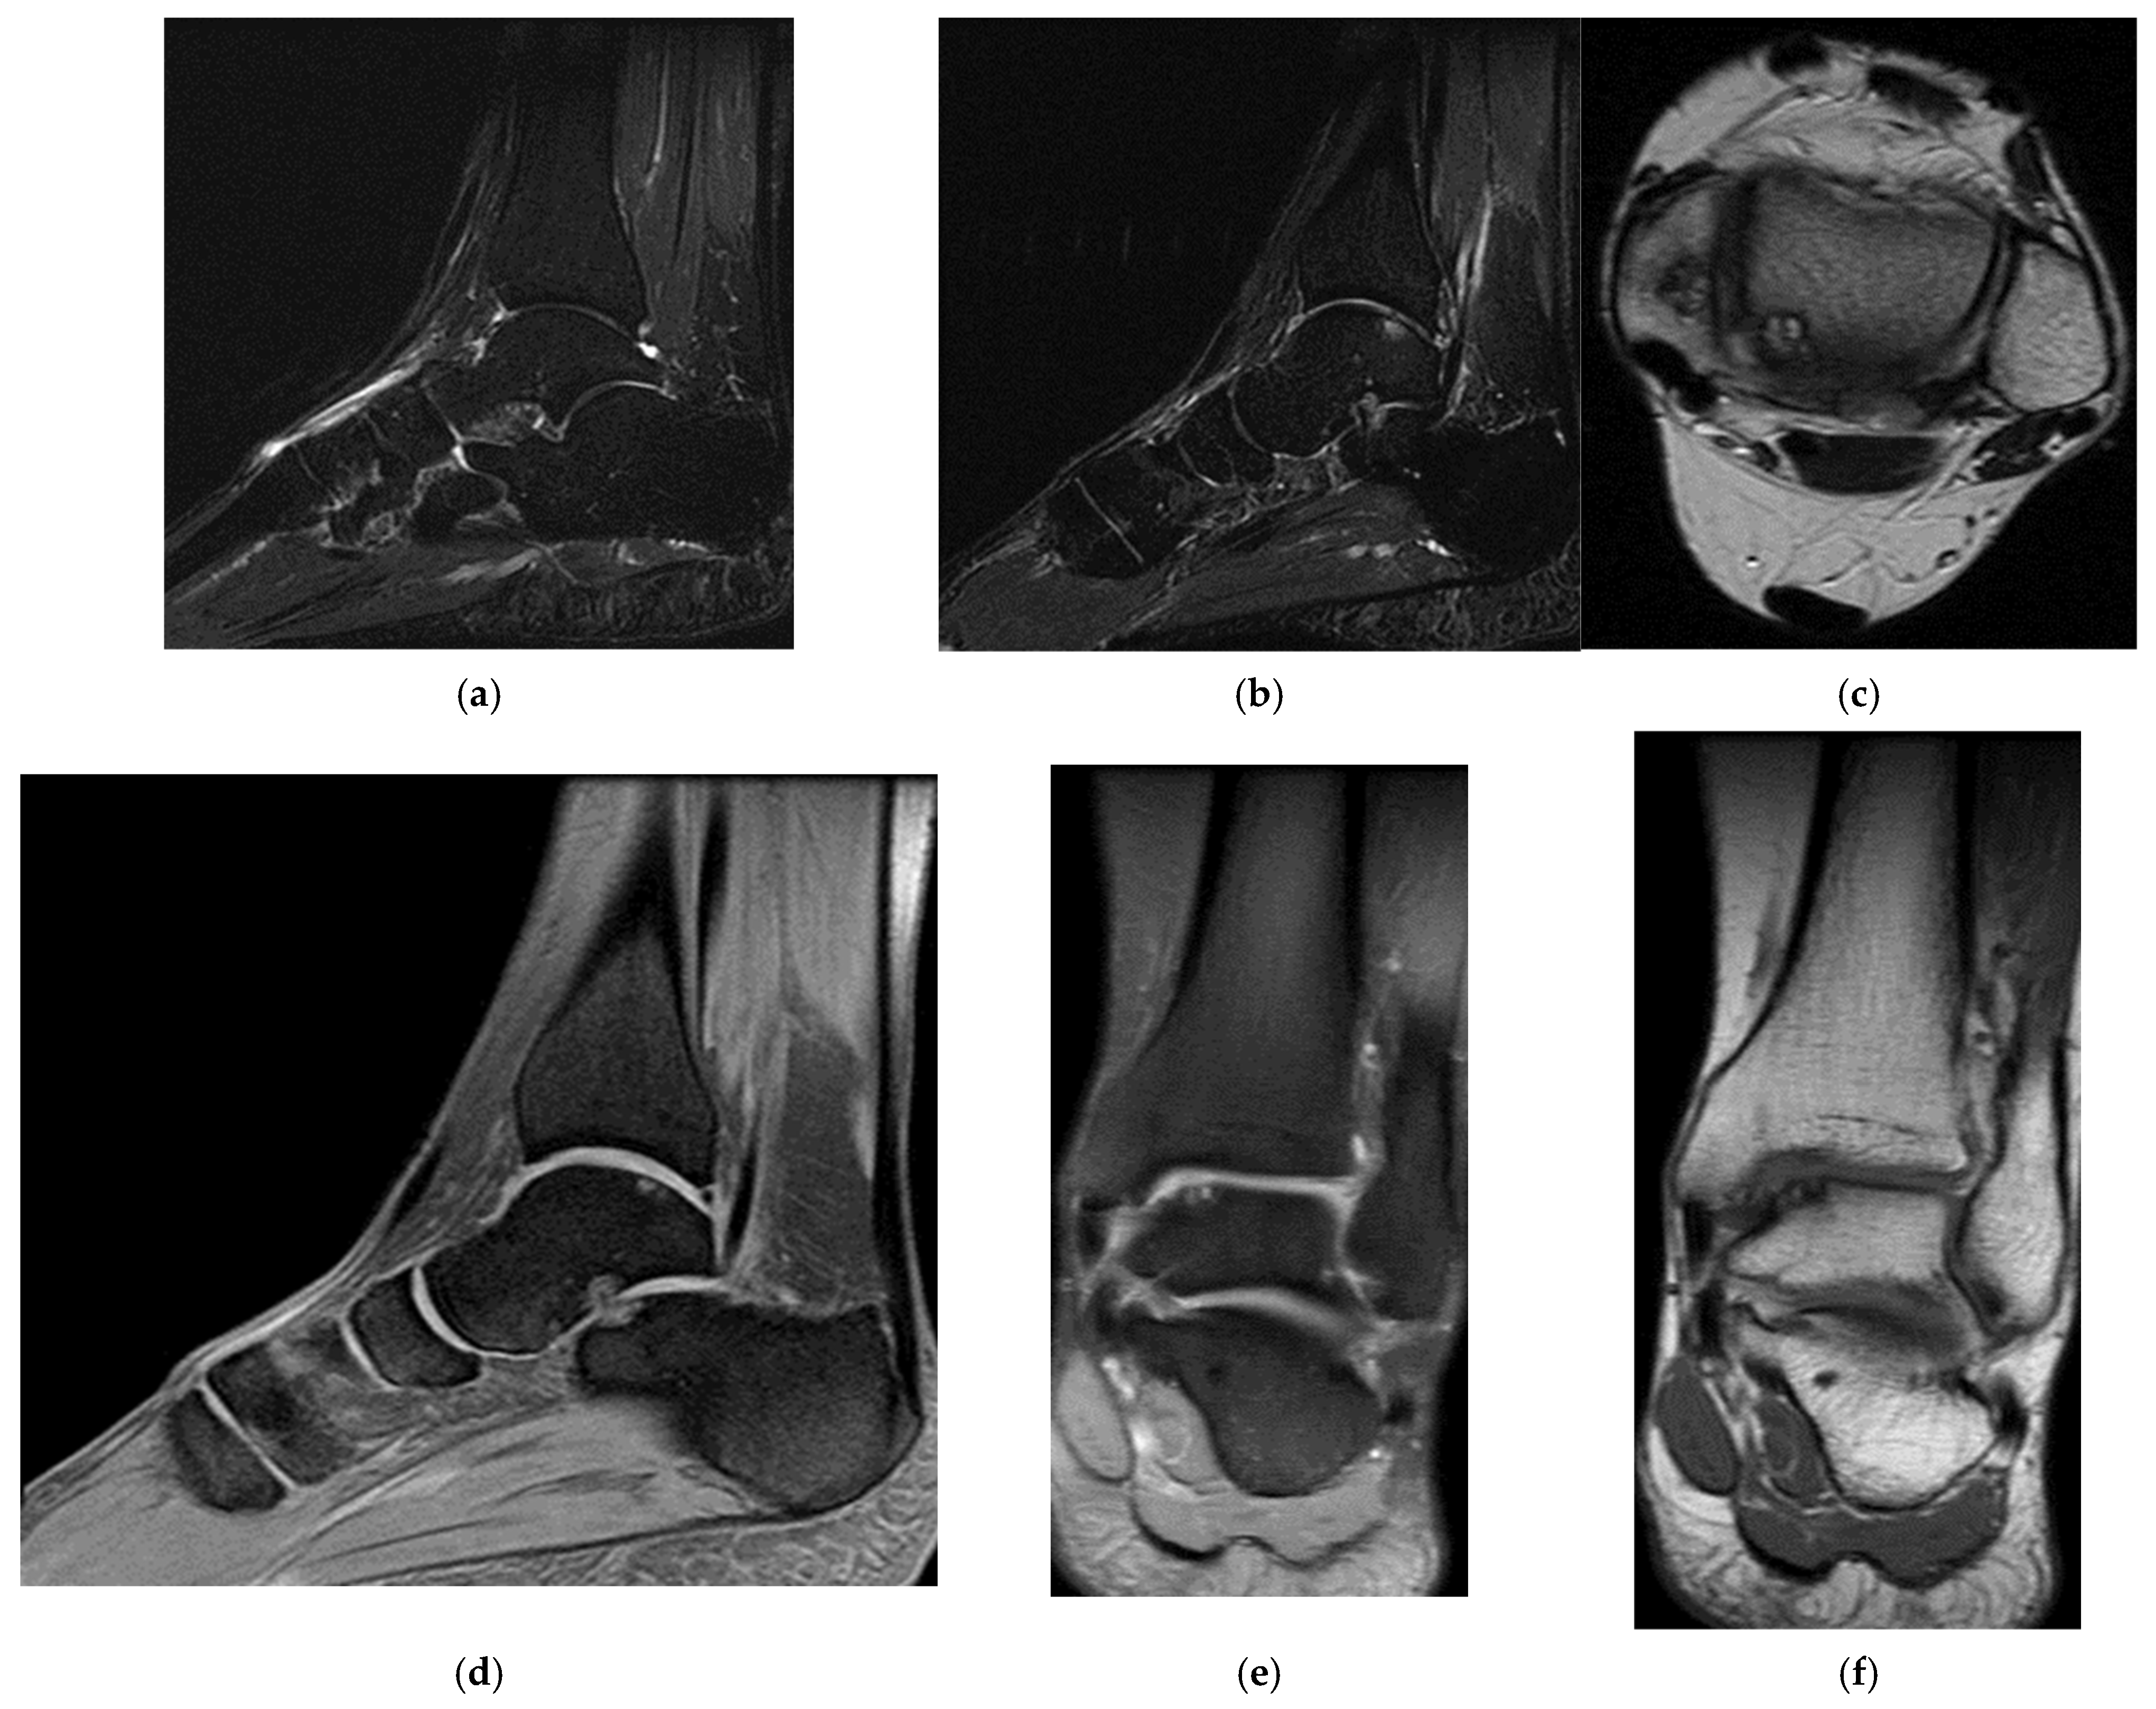

Three years post-trauma, the player develops symptoms of peripheral neuropathy with sensory and motor symptoms in the external popliteal sciatic nerve. Lumbar degenerative disc disorder or piriformis syndrome was suspected, and lumbar and pelvic MRI was performed.

The spinal MRI revealed no evidence of degenerative lumbar disc pathology or radiculopathy (Figure 5). Magnetic resonance imaging (MRI) and radiographic examination of the pelvis revealed an old avulsion injury with a detached bone fragment at the insertion site on the left ischial tuberosity, involving the semitendinosus, semimembranosus, and biceps femoris muscles (collectively referred to as the ischium-calf muscles). This condition has led to the development of pseudoarthrosis and bone edema at the level of the ischial tuberosity. The sciatic nerve is positioned tangentially to the inflammatory response. Despite the detachment, the bone fragment remains vascularized due to the maintained insertion of the ischial calf muscles, preventing it from becoming a bone splinter (Figure 6 and Figure 7).

(a) Spinal MRI: sagittal T2 fat sat acquisition, (b) spinal MRI: sagittal T2 acquisition, (c) spinal MRI: coronal T2 acquisition, (d) spinal MRI: axial T2 acquisition.

(a) Pelvic MRI: coronal stir acquisition, (b) pelvic MRI: sagittal PD fat sat acquisition, (c) pelvic MRI: sagittal PD fat sat acquisition, (d) axial stir acquisition, (e) axial stir acquisition, (f) axial T1 acquisition.

The pseudoarthritis secondary to the old ischial tuberosity avulsion can be visualized as follows:

- An old detached bone fragment with signal in the T1 and T2 ponderations, similar to the rest of the existing bone structures, but showing focal alterations of the PD fat sac and STIR hypersignal, indicating bone edema.

- Fluid accumulation in T2 hypersignal, T1 hyposignal, between the torn bone fragment and the remaining tuberosity

- The altered PD fat sac hypersignal in the sciatic nerve, adjacent to the inflammatory process, indicates changes suggestive of focal neuritis.

Surgery might be applied either for the surgical treatment of pseudoarthritis or the excision of the detached fragment with reinsertion of the ischial–calf muscles, both treatment variants were refused by the patients due to long-term postoperative recuperation, as the player was training for international competitions.

Treatment eventually consisted of rest and NSAIDs; the inflammatory process decreased in size and, consequently, contact with the sciatic nerve. The radicular phenomena progressively decreased until complete remission was achieved and returned to play after 3 weeks.